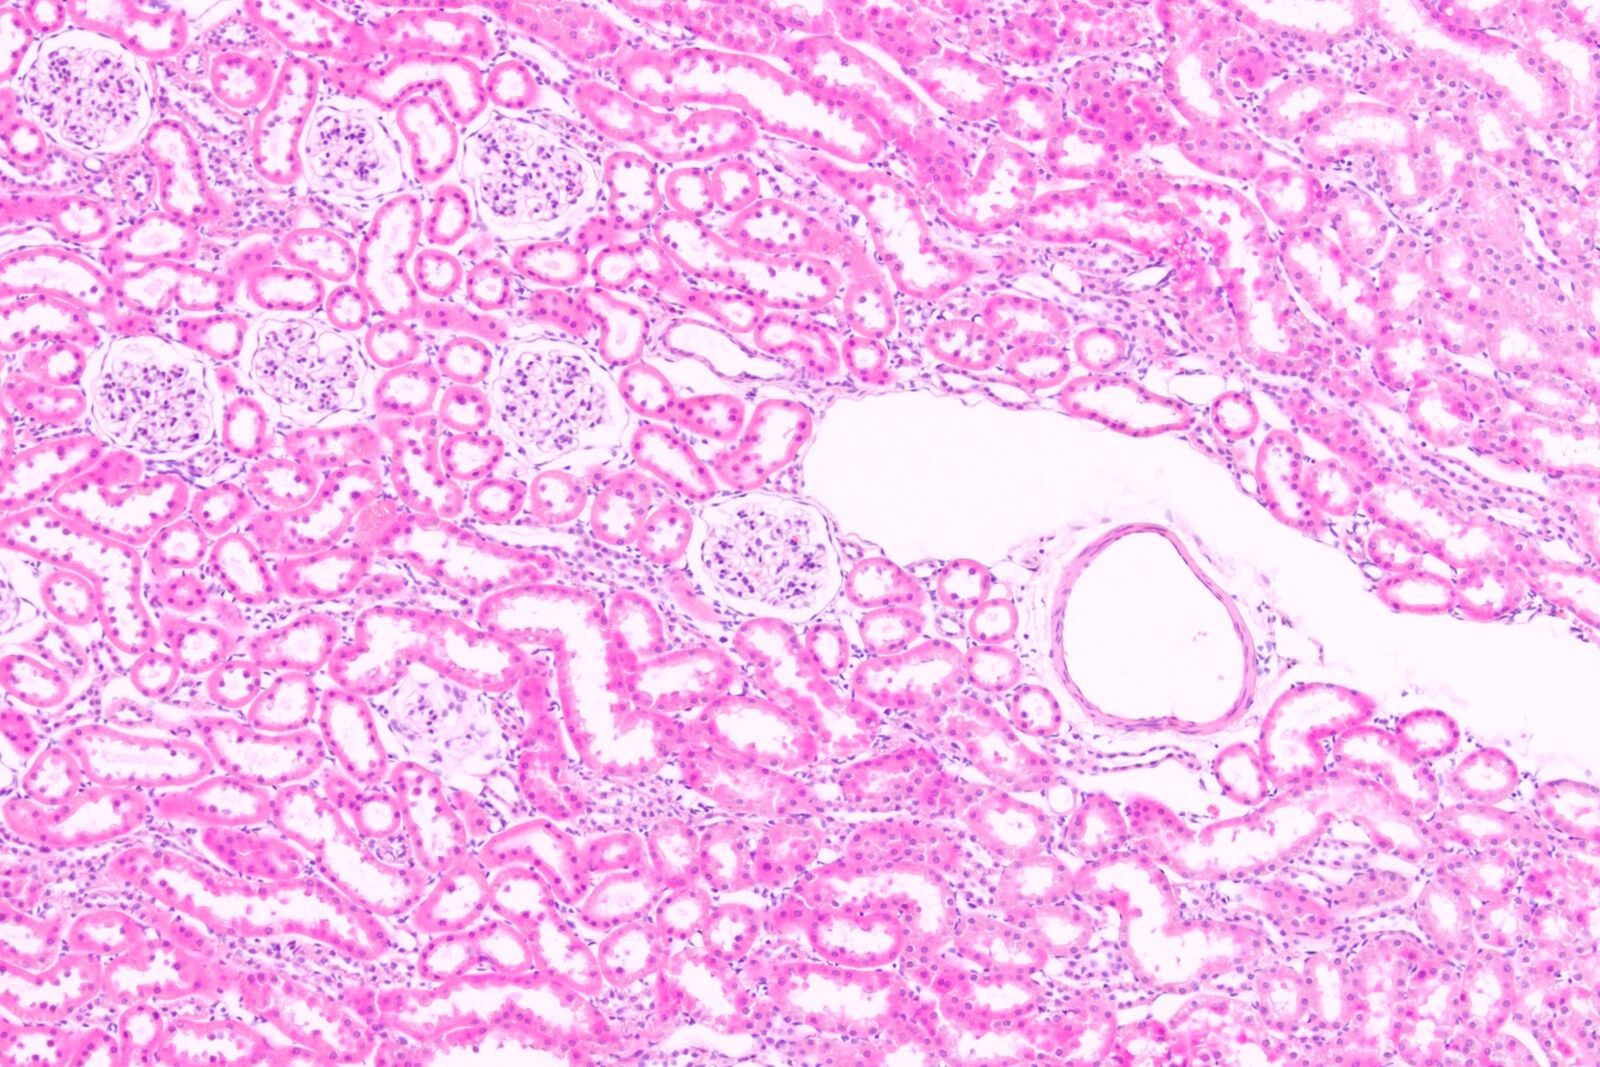

组织染色方法通过增强组织对比度,方便临床病理学与生命科学研究中的样本观察。传统方法需依赖 RGB 相机捕捉色彩编码信息,但其芯片滤光片矩阵设计常导致分辨率损失。Mica创新的 FluoSync 检测技术突破了这一限制,实现单次拍摄即可获得高分辨率 RGB 图像,并能在需要时无缝切换比色成像与荧光成像模式。此外,Mica还解决了组织学应用中的常见工作流难题,例如从快速概览到高倍观察的流畅切换。本应用指南将深入探讨组织染色技术及研究人员面临的成像挑战。

运用组织染色方法的价值在于其能展现组织的亚细胞细节。当实验室制备的新鲜组织切片未经染色时,使用常规显微镜在基础照明下记录的图像缺乏揭示关键细节所需的必要对比度。染色通过增强组织对比度来突显重要特征,从而帮助研究者更好得出结论,例如识别病理学异常。